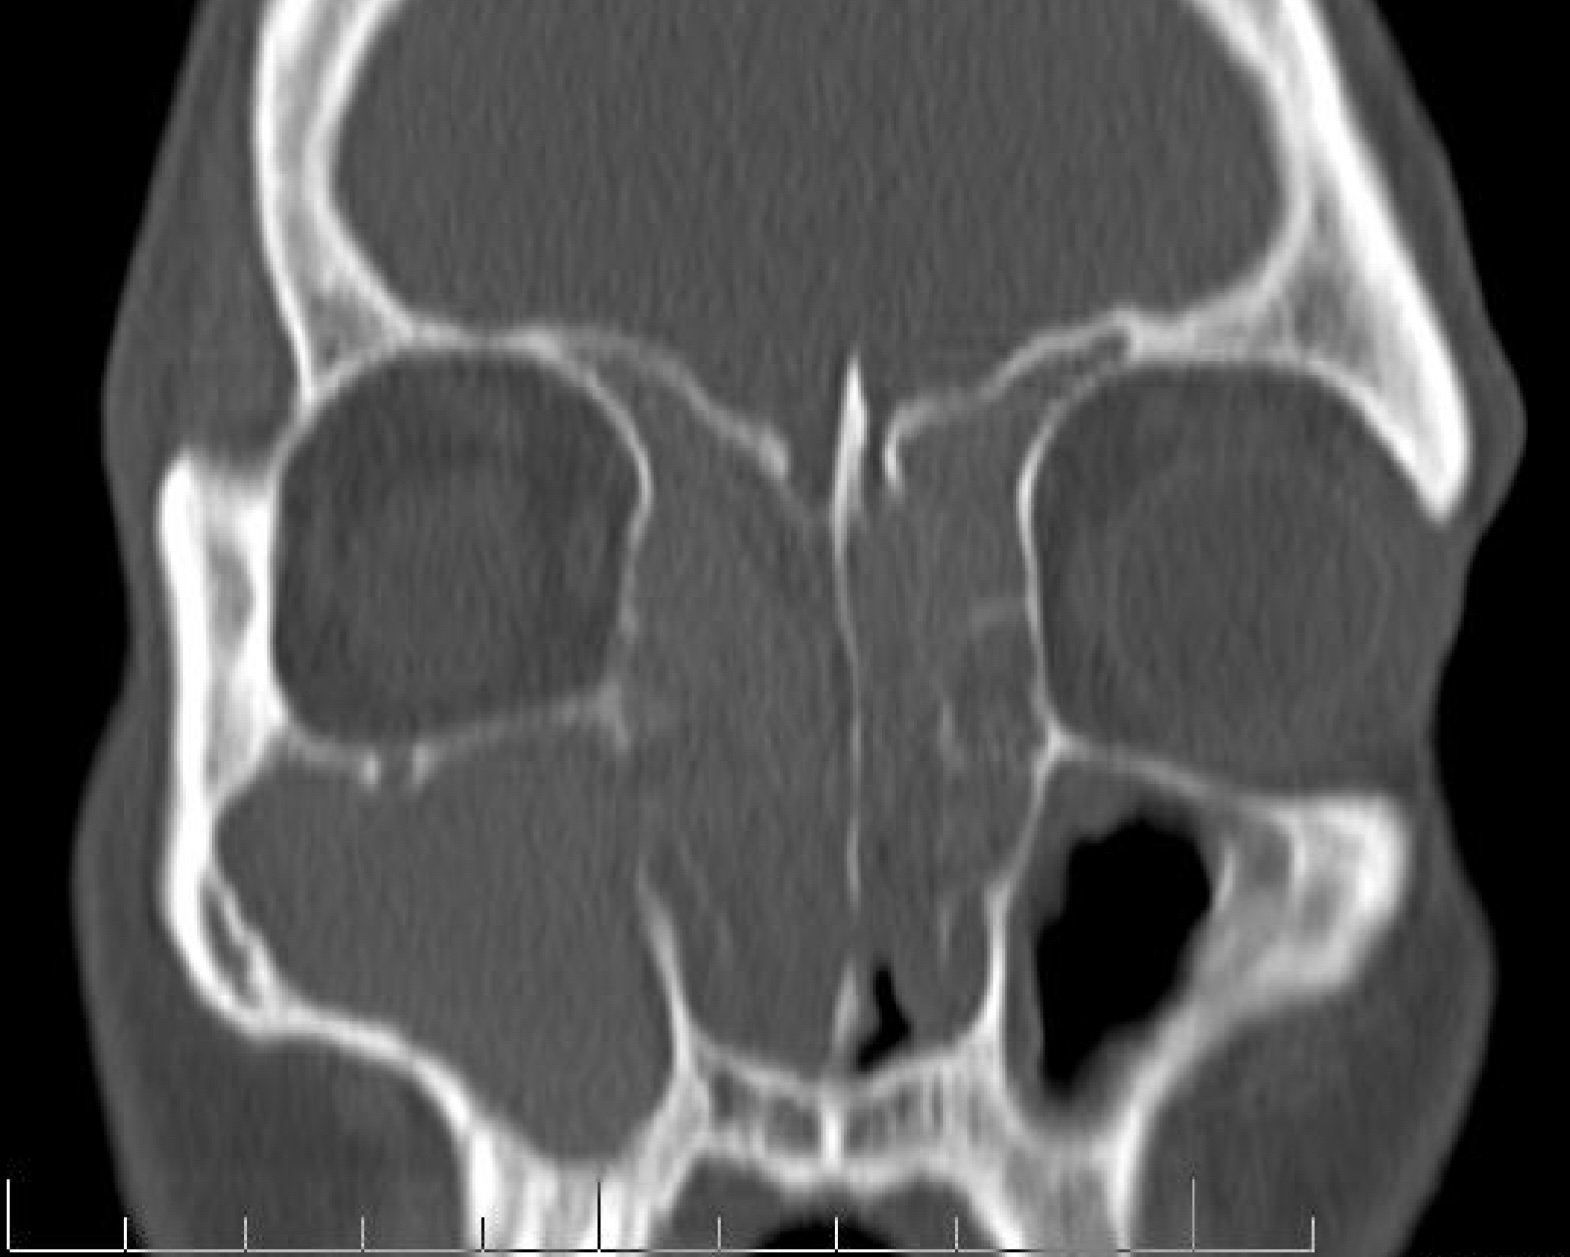

CT sinus scan showing severe chronic rhinosinusitis and nasal polyps through multiple sinus cavities

A sinus CT scan is the only way to objectively confirm chronic rhinosinusitis (chronic sinus inflammation). A scan shows the location and extent of disease, helps distinguish a deviated septum or enlarged turbinates from true sinus blockage, and gives us a detailed map to guide any needed procedures. We do not use contrast dye for routine sinus CT scans, which keeps the process quick and simple.